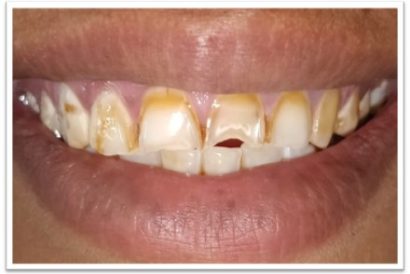

Before

After